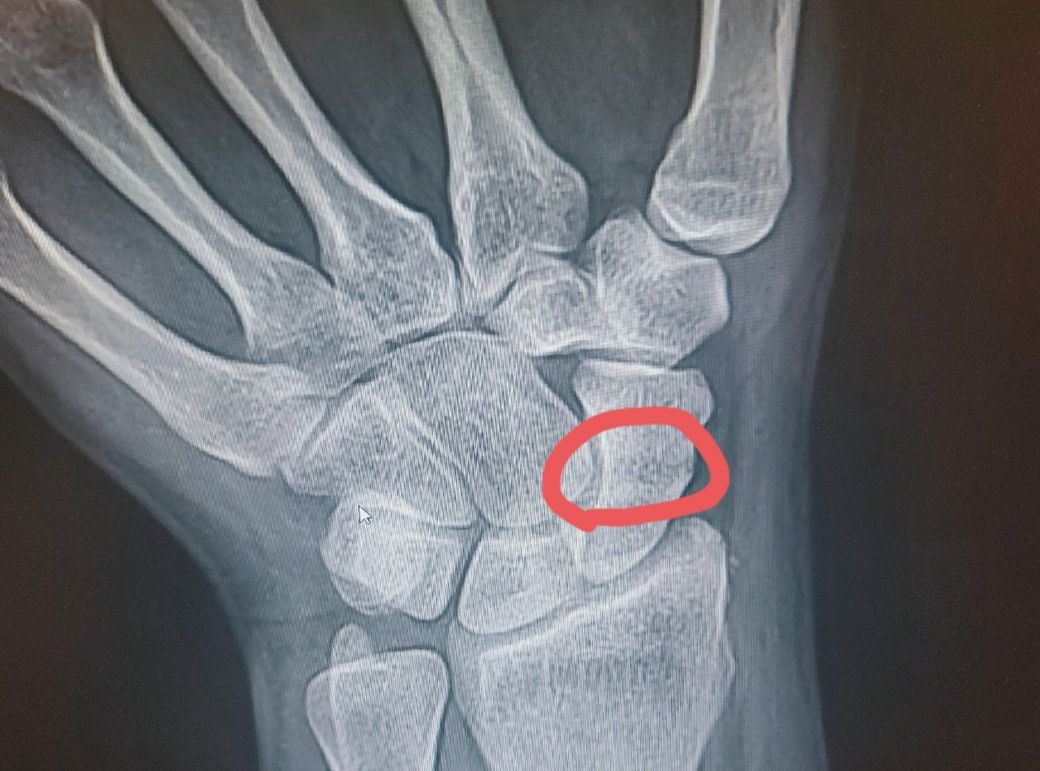

미세실금인가요?ㅠㅠ..씨티찍기싫고..진단서도안끊어줍니다ㅜ

판독부탁드립니다ㅜ저부위가 의심부위인데..

미세실금같다 이럽니다

현재 방사선 사진으로는 정확한 판독이 힘들어 주치의 선생님 말대로 ct 촬영이 필요할 수 있을 것 같습니다. 현재 상황에서 통증이나 불편감이 없다면 검사를 진행하지 않아도 되나 생활에 불편감이 있고 통증이 나타난다면 미세실금 및 주변조직의 손상이 있을 가능성도 배제할 수는 없습니다.

엑스레이상 실금처럼 보여지는 음영이 관찰되기는 하나 이것만으로는 정확한 진단을 내릴 수는 없을 듯합니다. 정확한 판단을 위해 CT 촬영이 필요한 상황으로 보여집니다. 골절의 여부에 따라 치료방침이 크게 달라지는 부분이오니 가능한 진단을 받으시는 것이 좋을 듯합니다.

미세 골절이라는 진단명 자체가 X-ray에서는 잘 보이지 않는 골절을 의미합니다. 결국 정확한 확인을 위해서는 추가적인 검사가 필요하지요. CT를 찍거나 골스캔 검사를 하는 방법이 있습니다. 중요한 것은 추가 검사를 통해 미세 골절로 진단한다고 해도 결국 치료는 같습니다. 수술을 하는 것도 아니고 깁스를 하고 뼈가 잘 붙을 때까지 기다리면 되지요. 지금 X-ray를 봐도 정확한 판단은 어렵습니다. 추가 검사가 부담스러우시다면 치료만 잘 받으셔도 될 듯 합니다. 실비보험이랑 관련된 문제라면 의료진 입장에서도 정확한 검사 없이 진단서를 작성해 드리기는 어렵답니다. 이 점은 양해 부탁드립니다.